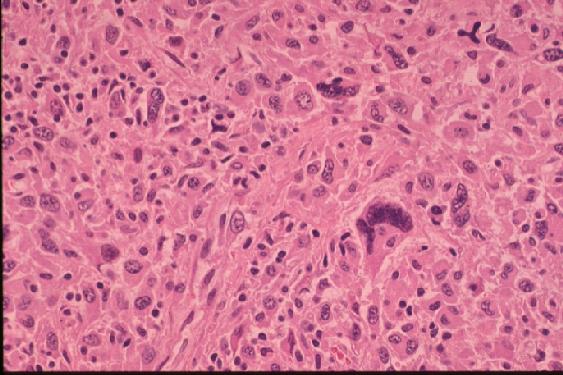

2. The left pleura is firmly adherent to the chest wall, and 330 ml of yellow pleural effusion is present in the left pleural cavity and 400 ml in the right. Pericardial space is firmly adhered. An elastic firm and smooth surfaced tumor is noted around the main trunk of the pulmonary artery (PA) and its main branches that measures about 9 x 6 x 5 cm in external dimension inclusively, accompanying a dumb-bell shaped, apparently separate mass on the posterior aspect of the left atrium that measures 8 x 6 x 3 cm in dimension. Anterior incision through right ventricular outflow tract and pulmonary trunk (jpg.43KB) reveals a tumor thrombus occupying the lumen of the main trunk and bilateral branches of the PA (elastic van Gieson and HE stains [jpg.34KB]), measuring about 7 x 4 x 3 cm in dimension, which in a retrograde fashion protrudes from the outlet at the level of the pulmonary valve into the lumen of the dilated right ventricle that measures 3.5 x 3.5 cm in dimension with smooth surface, and distally involves the upper lobe branch of the right PA 4.0 cm long from the hilus, and the upper and lower lobe branches of the left PA massively. The lumen of the right lower lobe branch of the right PA is free of invasion. The stent, which is consisting of four tandemly and one parallelly arranged metal pieces fairly evenly implanted in the lumen from the pulmonary valve to the hilum of the right PA, is being completely embedded in the tumor thrombus. The lumen of the stent, too, is almost completely obstructed by organizing tumor thrombus. On cut surface at the anterior aspect of the main PA, where the tumor is invading its wall and forming a nodular sessile mass that measures about 6 x 3.5 x 4 cm in dimension, the tumor is yellowish white, solid and uniform. The remaining thread from the previous operation is also identified there. The esophagus and ascending thoracic aorta and other mediastinal structures are free of involvement. Microscopic examination reveals diffuse proliferation of atypical spindle cells arranged in storiform pattern (ordinary type) (jpg.45KB) or diffuse proliferation of pleomorphic giant cells, including bizarre multinucleated giant cells (giant cell type) (jpg.47KB). Immunostains reveal distinct positivity of tumor cells for vimentin (jpg.44KB), questionable positivity for lysozyme, S-100 and alpha-1-anti-trypsin, and negative staining for desmin and SMA.

COMMENTS: This is a rare case of intimal sarcoma of the pulmonary artery in an elderly male person, terminating in the heart failure. The tumor, after surgical resection, recurred with local invasion and finally obstructed the lumen of the pulmonary artery completely, including the lumen of the implanted stent as well. No distant metastases were revealed at autopsy. Histological examination of the resected and autopsy specimen reveals that the tumor is composed mainly of the element suggestive of malignant fibrous histiocytoma.

The histological diagnoses of primary pulmonary artery sarcoma are various, including leiomyosarcoma, rhabdomyosarcoma, fibrosarcoma, myxosarcoma, osteosarcoma, undifferentiated sarcoma, malignant mesenchymoma, etc. One of the two cases reported by Nonomura et al (1988) was diagnosed with malignant fibrous histiocytoma by histologic, immunohistochemical and electron microscopic studies. The histologic, electron microscopic and immunohistochemical features of the current case, too, is consistent with those of malignant fibrous histiocytoma.